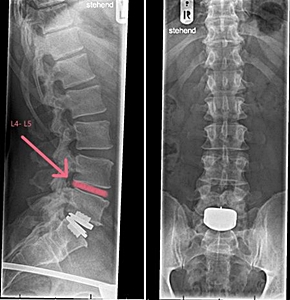

American standards only

allowed the

surgical implementation of

one lumbar ADR disc. However, I

had already undergone an

artificial disc replacement

(ADR) for one lumbar disc in

2014,

and it seemed I would now

require a second ADR, as

highlighted in red in the

image on the right.

My only option was again Europe

which had

been surgically implanting

multiple lumbar artificial

discs for two decades. |